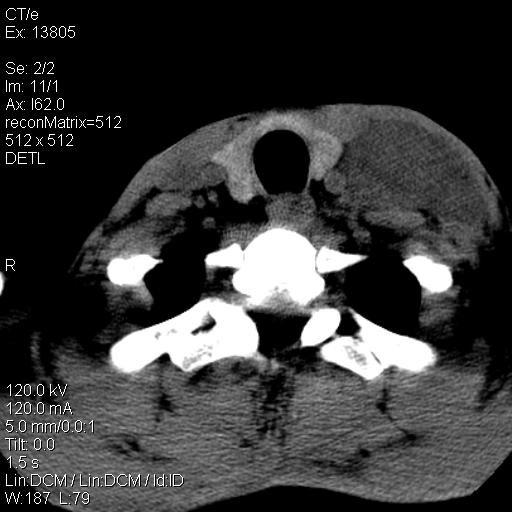

上腹部疼痛一月,呕吐10天,发现左侧颈部包快10天 胸部cr片未见明显异常。

左侧胸锁乳突肌下方、颈血管旁低密度肿块影,肿块密度尚均匀,边缘大部分清楚,邻近组织稍受压移位。考虑颈部神经鞘瘤可能性大。

颈部及腹膜后淋巴瘤可能性大